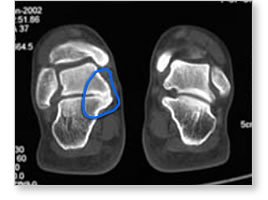

| If

it cannot be seen on a plain X-ray, the diagnosis of a tarsal

coalition becomes more obvious using a CAT scan. Note in the

scan here, the normal foot on the right and the bone connection

between the talus and calcaneus on the left. |